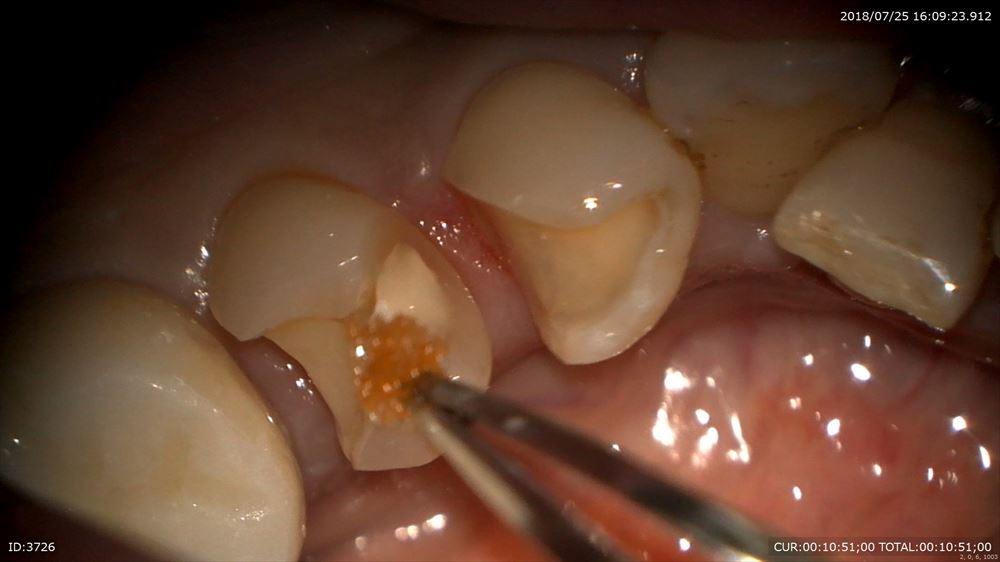

マイクロスコープを使用し無痛で除去

MTAセメントで神経を保護

ここまでで前回は終了。予後を数週見ます。